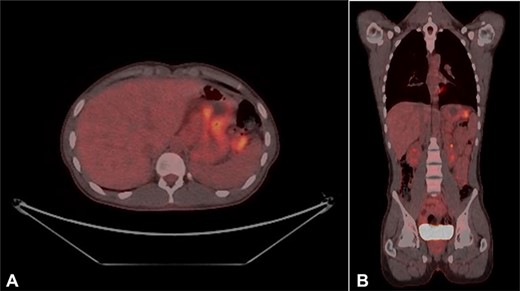

Urgent gastroscopy revealed a giant gastric ulcer in the antrum (Fig. 1) which was biopsied and sent for pathological investigation. The ulcer displayed no bleeding stigmata. He was started on eradication therapy for Helicobacter pylori. Pathology revealed a signet ring adenocarcinoma of the stomach (Fig. 2A and B). A computerized tomography (CT) scan (Fig. 3) showed a large mass in the distal stomach, and the ensuing positron emission tomography (PET) scan (Fig. 4) showed enlarged D1 perigastric lymph nodes with no obvious metastatic disease.

(A and B) PET scans (axial and coronal views) showing enlarged D1 perigastric lymph nodes (green arrows) and no apparent metastatic disease.